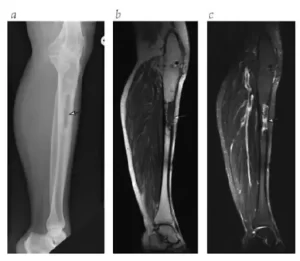

A osteomielite é uma infecção óssea crônica ou aguda que pode comprometer gravemente a estrutura, vascularização e função do osso, sendo uma das condições mais desafiadoras da ortopedia moderna. Pode ocorrer após fraturas expostas, cirurgias ortopédicas, infecções hematogênicas ou como consequência de implantes contaminados.

Osteomielite pós-traumática ou pós-cirúrgica;

Sequelas de infecção crônica com fístula e perda óssea segmentar;

Reconstrução de falhas ósseas extensas após erradicação da infecção.